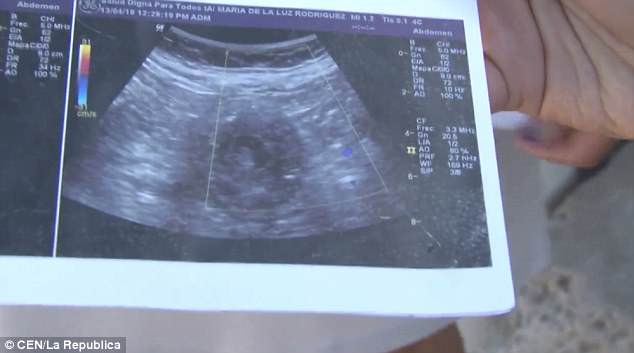

Η Μαρία Ντε Λα Λουζ έδειξε στους δημοσιογράφους υπερηχογραφήματα, τα οποία σύμφωνα με την ίδια επιβεβαιώνουν ότι είναι 6 μηνών έγκυος και περιμένει κοριτσάκι.

«Μου είπαν ότι είναι κορίτσι. Κοιτάξτε, μπορείτε να δείτε το πρόσωπό της», ανέφερε η 70χρονη γυναίκα από το Μεξικό.

Ένα από τα υπερηχογραφήματα της Μαρία Ντε Λα Λουζ.